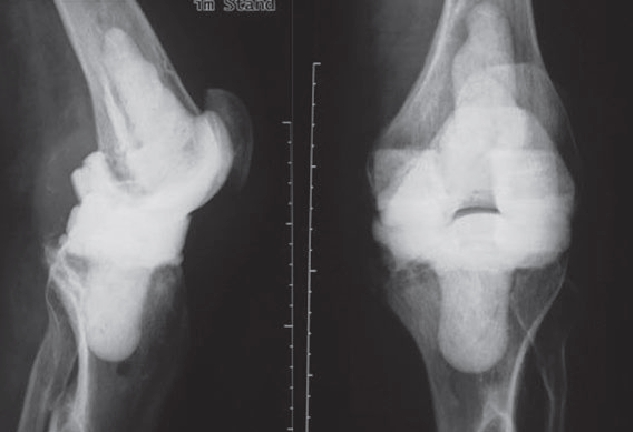

Generally, a distinction is made between acute and chronic infection. A form of chronic infection, the so-called low-grade infection, can also be the reason for premature loosening of the prosthesis. Since the bacteria multiply slowly, this infection is so weak that it is hardly noticed by the patient and also eludes laboratory tests, since it causes hardly any changes in the blood.

In order to diagnose these infections, tissue samples are taken from the joint in addition to a puncture, as only close cooperation between orthopedists, pathologists and microbiologists can ensure the correct diagnosis. In addition, we also devote ourselves to obviously infected prostheses, of course. These infections can occur shortly after the operation (so-called early infection up to 6 weeks postoperatively) but also years after the operation (as so-called late infection). In addition to the smallest entry points (e.g. an ulcerated toenail), serious infections such as pneumonia can also lead to bacteria colonizing the surface of the prosthesis. Patients with a limited immune system (e.g. diabetics, rheumatics) are particularly at risk. If an infection is noticed early enough after surgery, it is occasionally still possible to eliminate the infection without removing the prosthesis by carefully cleaning the wound and changing the moving parts.

However, infections often go unnoticed for many weeks, so that removal of the prosthesis is unavoidable. Depending on the pathogen and its sensitivity, a placeholder containing antibiotics is then implanted, which remains in place for 6 weeks. Antibiotics in tablet form must then also be taken for this period. However, it is not necessary for a patient to remain in the hospital during this entire period. If home care is not possible, for example, it is also possible to organize this in close cooperation with our social services. After 6 weeks it is generally possible to reimplant a prosthesis, provided that the blood values show that the infection is under control. Antibiotics must then be taken again for 6 weeks after surgery. Which antibiotics are taken is determined in close cooperation with colleagues in microbiology and clinical pharmacology, with whom regular rounds and therapy checks are carried out. These therapeutic measures are carried out in a special area of the clinic using the most modern methods.